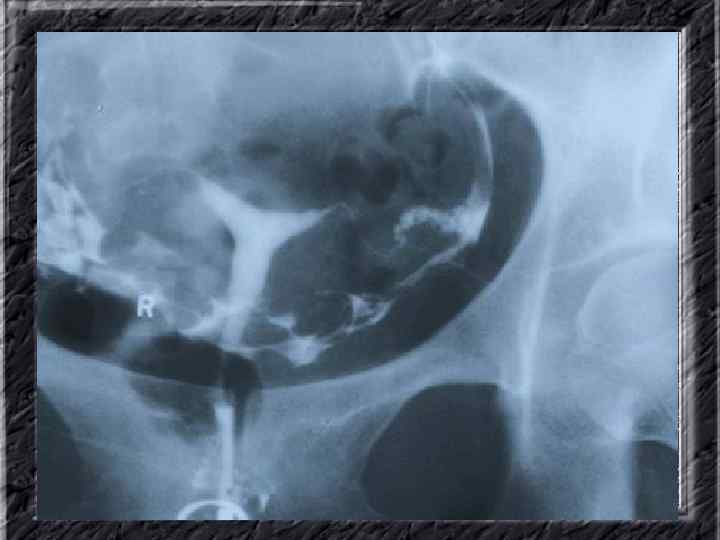

Названия слайдов: • • • Слайд 41. Лапароскопия: эндометриоидная киста яичника. Слайд 42. Лапароскопия: эндометриоидные гетеротопии на поверхности эндометриоидной кисты яичника. Слайд 43. Ультрасонография: поликистозное изменение яичника. Слайд 44. Серозная цистаденома яичника: внешний вид; макропрепарат. Слайд 45. Лапароскопия: цистаденома яичника. Слайд 46. Ультрасонография: папиллярная цистоаденома яичника, содержащая внутри папиллярные разрастания. Слайд 47. Ультраснография: многокамерная киста яичника (муцинозная цистаденома). Слайд 48. Лапароскопия: папиллярная цистаденома. Слайд 49. Ультрасонография: многокамерное жидкостное образование яичника, содержащее полиморфный солидный конгломерат — рак из муцинозной цистаденомы. Слайд 50. Рентгеноконтрастная сальпингография: нормальное наполнение и проходимость обеих маточных труб.